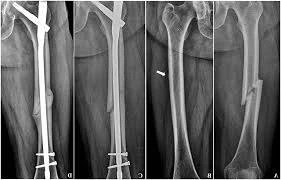

إن جراحة المسمار النخاعي هي تلك العملية التي يتم استخدامها من أجل تثبيت العظام المكسورة، فيكون من السهل تركيب المسمار للقصبة أو الفخذ أو العضد، وهذا بهدف الحاجة إلى تثبيت العظام مع التعافي السريع للمرضى، وهذه العملية تساعد في دعم العظام وتجعل عملية الشفاء أكثر سلاسة وهذا مع القدرة على المشي المبكر، عكس عملية الشريحة والمسامير التي يتم فيها انتظار المريض بعض الوقت لكي تلتئم العظام.

المسمار النخاعي هو عبارة عن جهاز على شكل طولي اسطواني ويكون نفس شكل العظام المصمم من أجل تركيبه لكي يتوافق مع التجويف الداخلي للعظمة، ودكتور العظام المتخصص في الركبة أو الكتف أو إدخاله من أقرب مفصل للعظام المكسورة بواسطة جرح صغير نسبيًا، حيث يدخل المسمار داخل التجويف الخاص بالنخاع العظمي ويكون على الأغلب مكون من مواد معدنية مثل الستانلس المقاوم للصدأ أو التيتانيوم.